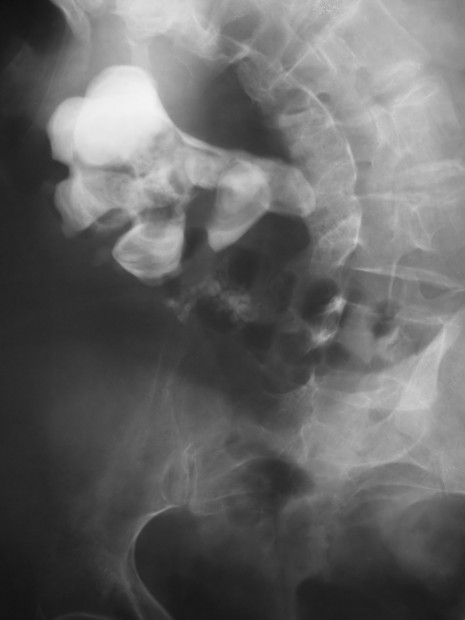

Příčinou renální koliky jsou nejčastěji močové kameny (konkrementy). Kolika se vyskytuje nejčastěji mezi 40 až 60 lety věku. Vyšší výskyt urolitiázy (kameny v močových cestách) je u mužů. Příznakem je krutá bolest v zádech (nefralgie), která vyzařuje do břicha, podbřišku směrem k močovému měchýři, u mužů mnohdy až do varlat. Propagace bolesti je daná podle výšky překážky v močových cestách. Projevuje se polakisurií, nevolností, opoceností, zvracením, neklidem, zástavou odchodu plynů a stolice. Nemocným nevyhovuje klid na lůžku, upřednostňují pohyb. Je patrný motorický neklid. Laboratorně je přítomna krev v moči, při urosepsi se objevují horečky. Bolest je kolikovitá, kdy je velmi krutá bolest střídaná úlevou, bolest zmírňuje teplo. Kolikovitá bolest je způsobena silnými křečovitými stahy hladkých svalů ve stěnách orgánu, který se snaží překážku vytlačit. Diagnostika spočívá v sonografickém vyšetření. Po odeznění akutního stavu se pak dále provádí vylučovací urografie či počítačová tomografie (CT). Léčba spočívá v podání spasmolytik, analgetik, antiflogistik a v infuzní terapii. Následně se odstraňuje kámen, přes močový měchýř tak zvanou ureterorenoskopií (URS) nebo litotrypsí (rázovou vlnou), či je přistoupeno k operačnímu řešení (nefrektomie). Pokud má nemocný horečky, je anurický, prvořadé je zajištění derivace močových cest, obvykle založením perkutánní nefrostomie (vývodu). Prevence další ataky spočívá v dietním opatření podle typu kamene a v pitném režimu. [2]

Zdroj: Autor Nevit Dilmen, Staghorn Kidney Stone 08779, licence Creative Commons BY-SA 3.0.

Obr. 3. Kameny v ledvině